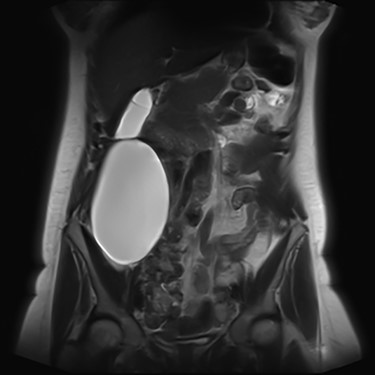

We present an extremely rare and isolated case of primary mixed serous and mucinous cystadenoma in a 49-year-old otherwise fit and healthy female patient. She was referred to our consultant with a history of discomfort on the right side of her abdomen for few years, which increased gradually with no other complains. The patient had further investigations conducted including computed tomography (CT) (Figs 1 and 2) that demonstrated the position and size of the lesion. The magnetic resonance imaging (MRI) revealed a large cystic lesion in the right retroperitoneal region shown in Figs 3 and 4. Her full blood count, inflammatory markers, urea and electrolytes and liver function tests were within the normal limit. Consequently, the patient had a laparoscopic resection of an isolated retroperitoneal cyst. At surgery, the cystic lesion seemed to be arising from mesentery and the lesion was dissected intact and completely excised. Histopathology revealed a benign mixed serous and mucinous cystadenoma as shown in Fig. 5. The patient was discharged from the hospital with no complications and fully recovered on follow-up review. Patient was discussed in a multidisciplinary team meeting and the recommendation was for no further management.

Serological investigations are not helping with providing a definitive diagnosis. Tumour markers such as, carbohydrate antigen (CA) 19–9, CA 15–3, CA 125, carcinoembryonic antigen (CEA), alpha feta protein have not been shown to be sensitive or specific. Some cases demonstrated an increase in CEA and CA 19–9 in associated with PRMC. However, these are isolated case studies. With regard to radiological investigation, the ultrasonography lacks specificity [11]. Radiological imaging, such as MRI and CT, plays an important role in describing and assessing the disease’s characteristics and the involvement of adjacent or distant structures of the mass. None of the modalities can exclude the malignant potential of the retroperitoneal masses [9], as the diagnostic value of CT and MRI is similar [12]. Predominantly male patients and the patients who present with solid nodules in the cyst on their radiology images have strong association with malignancy [13].